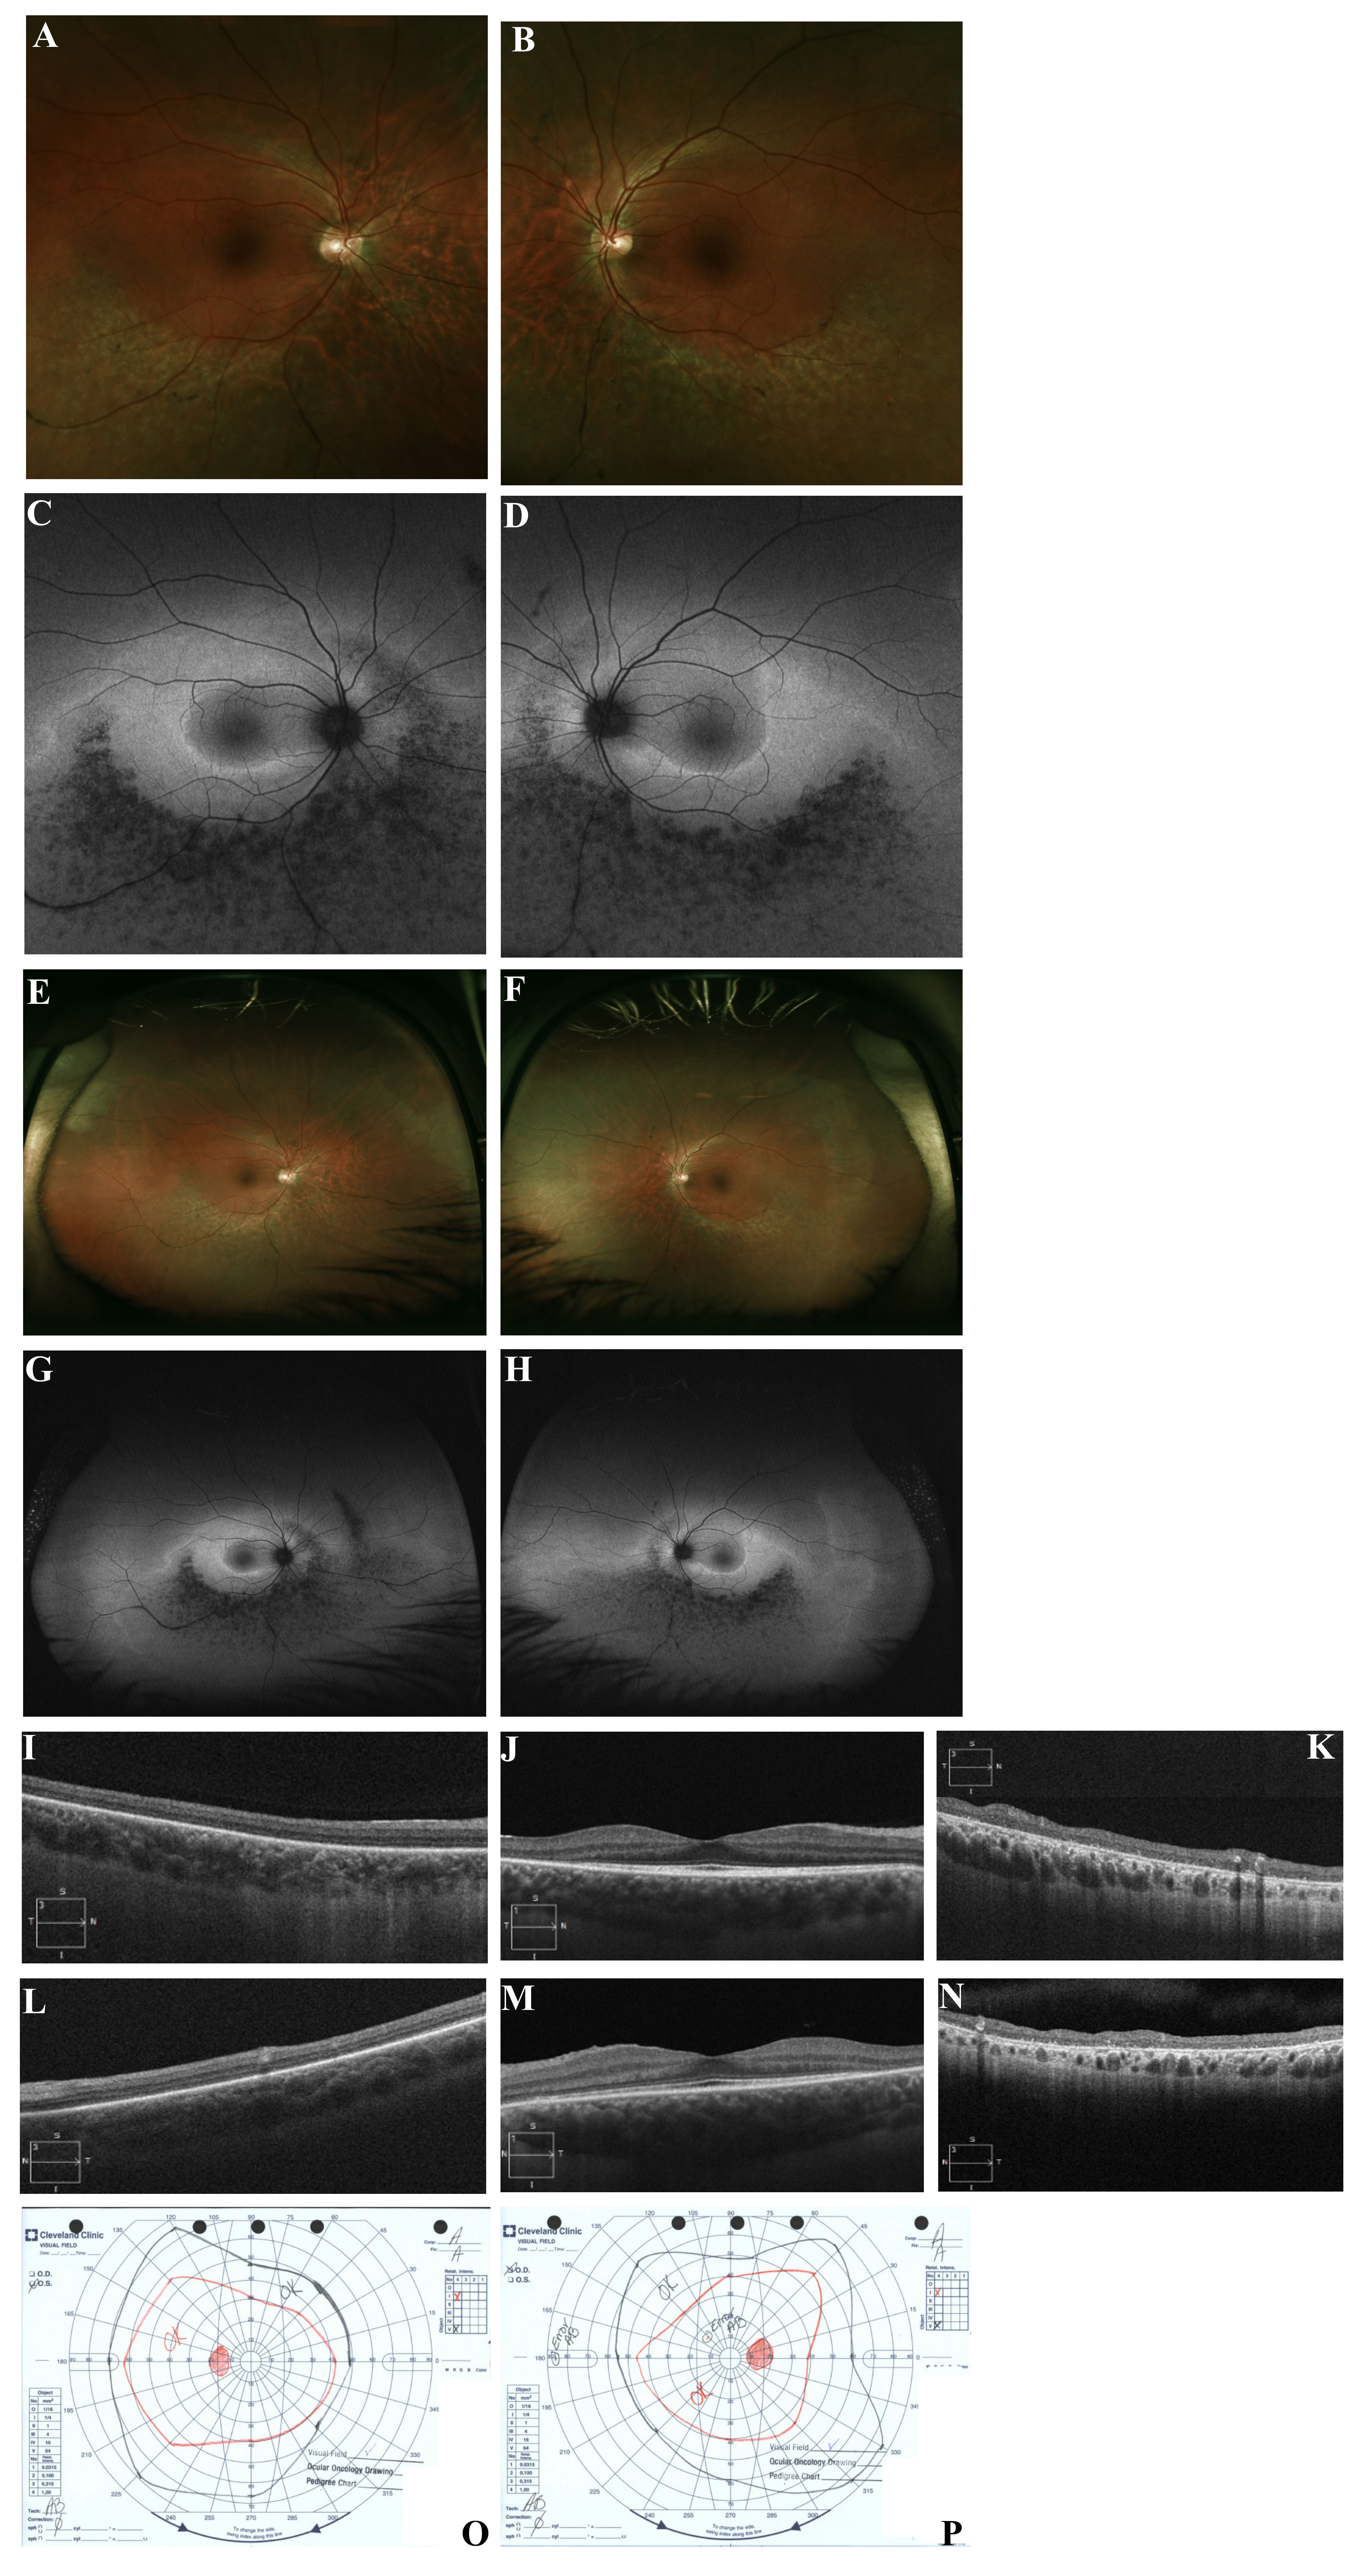

Figure 8. Clinical imagining of patient 8 with a c.325G>A mutation in RHO (p.Gly109Arg). A, E: Oculus dexter (OD) color photos showing RPE hypopigmentation and atrophic changes extending inferiorly from the inferior

arcade border to the periphery. B, F: Oculus sinister (OS) color photos showing RP RPE hypopigmentation and atrophic changes extending inferiorly from the inferior

arcade border to the periphery. C, G: OD fundus autofluorescence (FAF) fundus photos showing a linear hyper-autofluorescence (hyperAF) abutting the inferior edge

of the fovea. An OU patchy pattern of hypoautofluorescence (hypoAF) extending from the inferior border of the inferior arcade

into the inferior and inferonasal midperiphery. D, H: OS FAF fundus photos showing linear hyperAF abutting the inferior edge of the fovea. OU patchy pattern of hypoAF extending

from the inferior border of the inferior arcade into the inferior and inferonasal midperiphery. I: OD spectral-domain optical coherence tomography (SD-OCT) of the superior posterior pole showing retinal thinning and ellipsoid

zone loss of the superior posterior pole adjacent to the arcades. J: OD foveal SD-OCT showing a small island of preservation in the ellipsoid zone subfoveally with parafoveal loss of the ellipsoid

zone. K: OD SD-OCT of the inferior posterior pole showing marked retinal disorganization and RPE hyper-reflective round deposits

adjacent to the arcades with significant choroidal hyporeflective signal. L: OS SD-OCT of the superior posterior pole showing retinal thinning and ellipsoid zone loss adjacent to the arcades. M: OS foveal SD-OCT showing a small island of preservation in the ellipsoid zone subfoveally with parafoveal loss of the ellipsoid

zone. N: OS SD-OCT of the inferior posterior pole showing marked retinal disorganization and RPE hyper-reflective round deposits

adjacent to the arcades with significant choroidal hyporeflective signal. O: OS Goldman visual field showing mild nasal constriction. P: OD Goldman visual field showing small superior defects and mild temporal constriction.